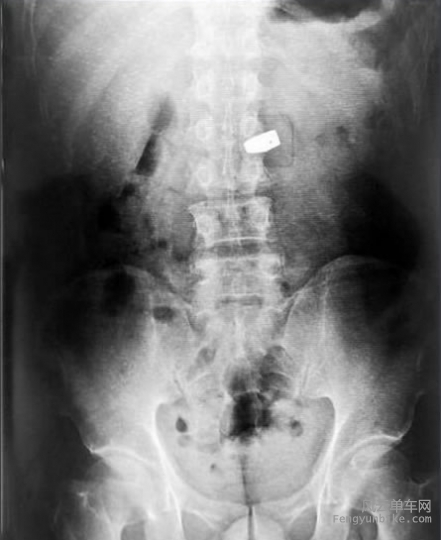

12月26日消息,一名中国女游客秦某,在泰国曼谷珠宝展上趁人不备,把一颗价值200万人民币的6克拉钻石囫囵吞下。警方通过X光,找到位于其大肠中的钻石,并让医生使用肠镜等器械,将钻石从该女子的肠中取出。

警方通过X光,找到位于其大肠中的钻石,并让医生使用肠镜等器械,将钻石从该女子的肠中取出。